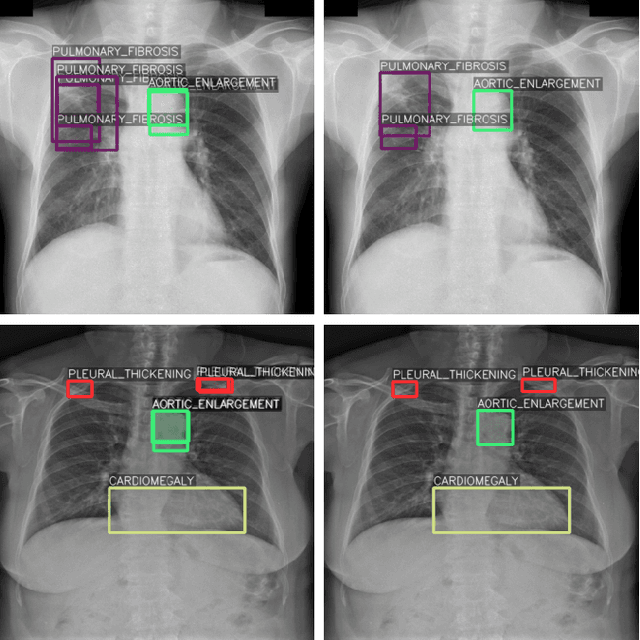

Abstract:One of the largest problems in medical image processing is the lack of annotated data. Labeling medical images often requires highly trained experts and can be a time-consuming process. In this paper, we evaluate a method of reducing the need for labeled data in medical image object detection by using self-supervised neural network pretraining. We use a dataset of chest X-ray images with bounding box labels for 13 different classes of anomalies. The networks are pretrained on a percentage of the dataset without labels and then fine-tuned on the rest of the dataset. We show that it is possible to achieve similar performance to a fully supervised model in terms of mean average precision and accuracy with only 60\% of the labeled data. We also show that it is possible to increase the maximum performance of a fully-supervised model by adding a self-supervised pretraining step, and this effect can be observed with even a small amount of unlabeled data for pretraining.